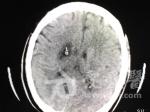

分享【一般资料】 患者,男,57岁,已婚,汉族 【主诉】 以“左侧肢体感觉减弱伴进行性肌力下降12天”入院。 【病史】 患者于6月9日感头痛、头晕,乏力伴左侧肢体感觉减弱等不适,自以为是中暑,自行服用藿香正气水后无明显好转,遂饮白酒约100ml后入睡,次日又因和家人怄气再次饮酒约150ml,11日晨起后患者不适无明显好转,并出现吐字不清等情况,患者和家人以为系患者饮酒后醉酒反应,未予重视。患者左侧肢体乏力等全身不适感呈加重。故于15日就医于外院,行头颅CT检查示:腔隙性脑梗死。给予口服脑得王胶囊、脉血康、晕痛定,静脉推注小牛血去蛋白提取物注射液等对症治疗后症状反而加重,出现口角歪斜、进食漏饭、左上肢瘫痪、左下肢活动无力等症状。现患者为进一步治疗于6月20日来我院就诊,门诊以:腔隙性脑梗死收住院。入院后患者神经科 【查体】 神志清,回答问题尚流利,吐字稍含糊,角膜反射存在,双侧瞳孔等大等圆,对光反射灵敏、口角向左偏斜,伸舌左偏,能配合张口、皱眉、皱额、瞬目、示齿等动作。不能配合鼓腮、吹哨动作。左上肢张力低,肌力0级,左下肢张力稍低,肌力4级,左侧肢体温度觉、触觉减退,左侧腹壁反射减弱。颈无抵抗,病理征未引出。由于患者发病来症状进行性进展,遂复查头颅CT,结果梗死灶明显增大(具体见CT涂片)。 【讨论】 1患者为什么会梗死灶增大?与用多种活血化瘀药有关还是与饮酒有关?静脉推注小牛血去蛋白提取物注射液:可增强组织细胞对氧及葡萄糖摄取与利用作用,改善细胞乏氧状态和机体内环境,增加心、脑、肝等脏器的血流量,改善微循环。脉血康:实验证明,本品能有效抑制血栓形成和血小板粘附,明显缩短红细胞电泳时间,降低血清胆固醇TC及血清甘油三酯TG,较强的延长血浆复钙,凝血酶原时间,改善微循环,具强的纤溶活性和抗凝血活性。这里有一个比较明显的问题,那就是对于急性脑血管疾病发作的病人首先应测量血压,然后应补充血糖检查以及进行凝血功能检查。对于该患者,还应该进行脑血管造影,这样才能了解血栓和栓子的准确位置。在缺血性卒中最初发生的48小时之内除了阿司匹林之外的其它抗凝药物是不推荐使用的,因为它们都有可能造成缺血性损伤的进一步加重。对急性患者进行一般支持疗法时也应当注意,过多的液体进入神经元可使缺血性损伤进一步加重。理论上降低血压可减少患者梗死后出血危险性,防止脑血管进一步损害,并预防脑血管进一步损害。但血压低会降低脑灌注压。脑卒中后脑血流自动调节功能受损,缺血半暗带的脑血流量与平均动脉压呈正相关,血压升高是脑卒中机体的一种代偿反应,目的要维持脑灌注压。若血压下降过快将使脑部供血减少,使得缺血或梗死的范围扩大,反之,特别是使用了溶栓药物治疗以后,高血压又会使脑出血的发病危险增加。因此,高血压病人的处理,不仅要维持适度的脑灌注压,还要防止高血压对患者的损害。高血糖能加重脑组织的损害,加重缺血脑组织的神经元坏死,扩大梗死灶范围,使病死率增加。因此也应注意病人的血糖标准。由于腔隙性脑梗死病灶小,一般不引起占位效应,脱水降颅内压无效,故若无明显颅内高压症,应避免使用脱水、利尿剂,以防血液进一步浓缩,使脑梗死症状加重。脑缺血发生后,半暗带区神经元面临两种结局,一种是局部微环境改善情况下,功能受损的神经元重新恢复,另外一种是局部微环境持续恶化而诱发神经元凋亡,是梗死灶扩大和迟发性神经元损伤的主要机制。下一步如何治疗?血压若无明显升高,一般不宜降压,但是当收缩压高于220mmHg、舒张压高于120mmHg或平均动脉压高于130mmHg时必须要采取降压,应及时应用降压药将血压逐渐降至卒中前水平或150~160mmHg/90~100mmHg左右。增加脑血流量,改善脑微循环。使用脑细胞活化药通过阻断由缺血所致各种有害病理过程的发生,从而防止由局部缺血所引起的脑损害,减少脑细胞死亡和促进功能恢复。加强支持治疗以及并发症的处理。

1患者为什么会梗死灶增大?与用多种活血化瘀药有关还是与饮酒有关? 静脉推注小牛血去蛋白提取物注射液: 可增强组织细胞对氧及葡萄糖摄取与利用作用,改善细胞乏氧状态和机体内环境,增加心、脑、肝等脏器的血流量,改善微循环。 脉血康: 实验证明,本品能有效抑制血栓形成和血小板粘附,明显缩短红细胞电泳时间,降低血清胆固醇TC及血清甘油三酯TG,较强的延长血浆复钙,凝血酶原时间,改善微循环,具强的纤溶活性和抗凝血活性。 这里有一个比较明显的问题,那就是对于急性脑血管疾病发作的病人首先应测量血压,然后应补充血糖检查以及进行凝血功能检查。 对于该患者,还应该进行脑血管造影,这样才能了解血栓和栓子的准确位置。 在缺血性卒中最初发生的48小时之内除了阿司匹林之外的其它抗凝药物是不推荐使用的,因为它们都有可能造成缺血性损伤的进一步加重。对急性患者进行一般支持疗法时也应当注意,过多的液体进入神经元可使缺血性损伤进一步加重。 理论上降低血压可减少患者梗死后出血危险性,防止脑血管进一步损害,并预防脑血管进一步损害。但血压低会降低脑灌注压。脑卒中后脑血流自动调节功能受损,缺血半暗带的脑血流量与平均动脉压呈正相关,血压升高是脑卒中机体的一种代偿反应,目的要维持脑灌注压。若血压下降过快将使脑部供血减少,使得缺血或梗死的范围扩大,反之,特别是使用了溶栓药物治疗以后,高血压又会使脑出血的发病危险增加。因此,高血压病人的处理,不仅要维持适度的脑灌注压,还要防止高血压对患者的损害。 高血糖能加重脑组织的损害,加重缺血脑组织的神经元坏死,扩大梗死灶范围,使病死率增加。因此也应注意病人的血糖标准。 由于腔隙性脑梗死病灶小,一般不引起占位效应,脱水降颅内压无效,故若无明显颅内高压症,应避免使用脱水、利尿剂,以防血液进一步浓缩,使脑梗死症状加重。 脑缺血发生后,半暗带区神经元面临两种结局,一种是局部微环境改善情况下,功能受损的神经元重新恢复,另外一种是局部微环境持续恶化而诱发神经元凋亡,是梗死灶扩大和迟发性神经元损伤的主要机制。 上述的每一步错误都有可能导致患者的梗死面积扩大,使得病情加重。个人认为,使用的药物并不足以导致梗死面积的改变,所以应该与患者饮酒有很大关系。 2下一步如何治疗? 血压若无明显升高,一般不宜降压,但是当收缩压高于220mmHg、舒张压高于120mmHg或平均动脉压高于130mmHg时必须要采取降压,应及时应用降压药将血压逐渐降至卒中前水平或150~160mmHg/90~100mmHg左右。 增加脑血流量,改善脑微循环。 使用脑细胞活化药通过阻断由缺血所致各种有害病理过程的发生,从而防止由局部缺血所引起的脑损害,减少脑细胞死亡和促进功能恢复。 加强支持治疗以及并发症的处理。

梗死扩大原因: 1.外在因素:饮酒、非正规治疗 2.内在因素:局部血管初期为狭窄,逐渐为闭塞。其发展过程是诸多因素参与的病生理变化。 治疗 1.吸氧 2.调控血压:维持在基础血压或稍高水平。 3.扩容:降低血液黏稠性,还可增加血容量维持血压 4.抗凝:阿司匹林、氯比格雷、低分子肝素等。 5.改善脑代谢药物 6.合并症、并发症及其他脏器病变的预防和治疗,营养支持。 7.瘫痪肢体的功能位及被动运动 具体治疗应根据病人的具体情况个体化治疗。

我考虑第一次行颅脑CT有梗塞灶,不知是否是责任梗塞灶,第二次已经发病12天了,接近颅脑CT的模糊效应期,但这个病灶对比第一次的CT应该是新鲜的,是瘫痪的原因,可以行颅脑MRI检查,看两次病灶的密度值有无一致。治疗应该抗血小板、抗凝、活血化瘀及稳定血压、血脂积极治疗,根据家庭情况看能否用起必存,效果应该不错的。 和应用药物、饮酒都无关,就是耽误治疗,错过时机了。